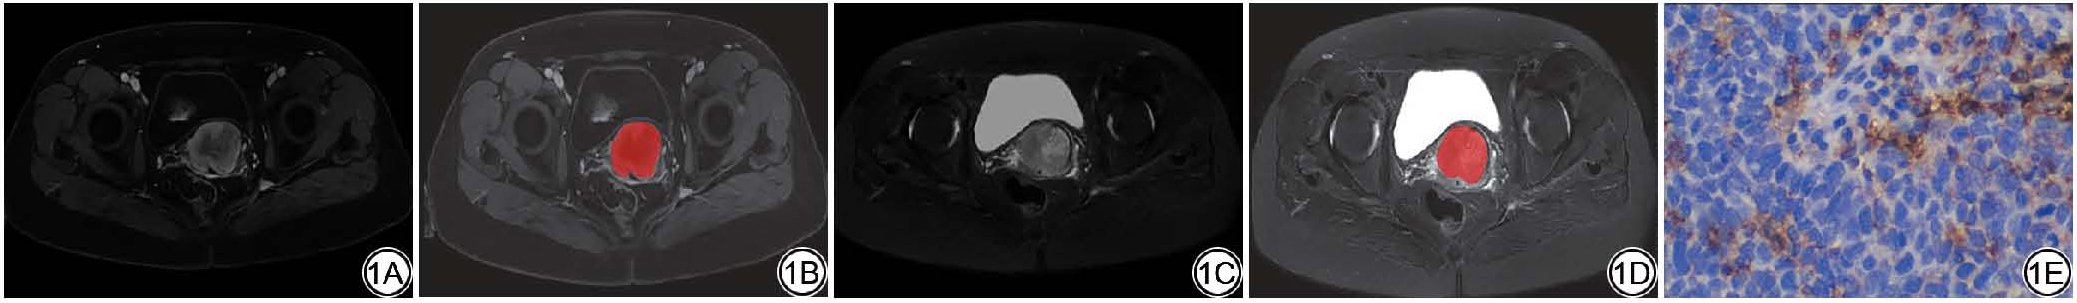

图2  女,55岁,宫颈鳞癌,PD-L1高表达。2A~2B:对比增强T1WI横截面图像(2A)及ROI勾画示意图(2B);2C~2D:脂肪抑制T2WI横截面图像(2C)及ROI勾画示意图(2D);2E:免疫组化染色图像(× 40)。PD-L1:程序性死亡受体配体1;ROI:感兴趣区。

Fig. 2  Female, 55 years old, cervical squamous cell carcinoma, high expression of PD-L1. 2A-2B: Cross section of contrast enhancement-T1WI image (2A) and schematic diagram of ROI sketch (2B); 2C-2D: Cross section of fat suppression-T2WI image (2C) and schematic diagram of ROI sketch (2D); 2E: Immunohistochemical staining image (× 40). PD-L1: programmed death-ligand 1; ROI: region of interest.